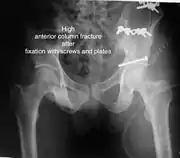

High anterior column fracture after fixation with screws and plates

The final management depends on the size of the fragment(s), stability and congruence of the joint. In some cases traction for six to eight weeks may be the only treatment required; however, surgical fixation using screw(s) and plate(s) may be required if the injury is more complex. The latter treatment will be called for if bone fragments do not fall into place, or if they are found in the joint, or if the joint itself is unstable.